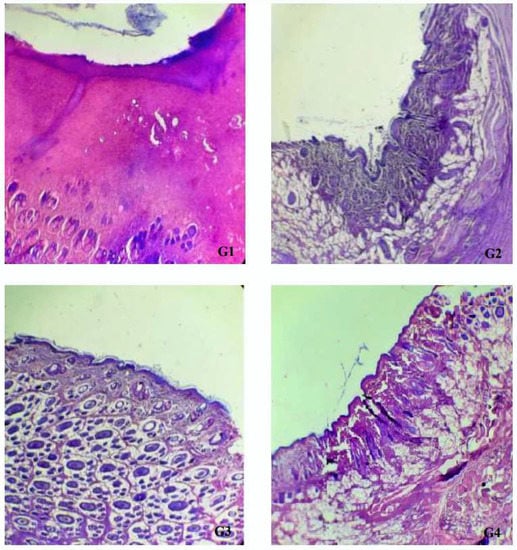

| Experimental Group | Wound Area (cm2) and Percentage of Wound Contraction | Epithelization Period (Days) | ||||

|---|---|---|---|---|---|---|

| Day 0 | Day 4 | Day 8 | Day 12 | Day 16 | ||

| Positive control (MEBO®) (G1) | 4.03 ± 0.70 *G3 | 3.43 ± 0.76 *G3 (15.33%) | 2.37 ± 0.40 *G3 (41.00%) | 0.56 ± 0.31 (86.50%) | 0.19 ± 0.12 (95.5%) | 11.50 ± 1.80 |

| Negative control (untreated group) (G2) | 3.82 ± 0.33 | 2.86 ± 0.48 (25.33%) | 2.13 ± 0.48 *G3 (44.17%) | 0.52 ± 0.53 (85.33%) | 0.19 ± 0.18 (94.67%) | 12.33 ± 1.88 |

| Ointment base control (G3) | 2.47 ± 0.36 *G1,G4,G2 | 2.13 ± 0.51 *G1,G4 (12.17%) | 1.41 ± 0.12 *G1,G2 (41.83%) | 0.23 ± 0.05 (90.17%) | 0.15 ± 0.09 (94.00%) | 11 ± 1 |

| MEO 2% (G4) | 3.56 ± 0.77 *G3 | 3.17 ± 0.42 *G3 (9.83%) | 2.11 ± 0.5 (40.83%) | 0.44 ± 0.12 (87.50%) | 0.17 ± 0.06 (95.00%) | 11.83 ± 1.07 |